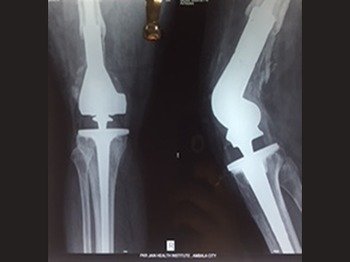

One of the most common joint replacement surgery in India. Only the worn out surfaces of the femur, tibia and patella (bones forming the knee joint) are reshaped, resurfaced and replaced with two metallic implants and a centre plastic piece.